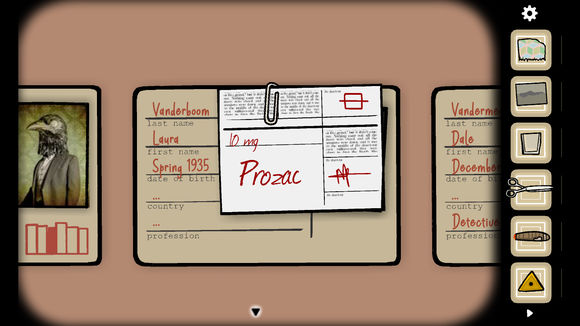

拿到布片,我们已经获得了全部5种证据,打开柜子上的case23,把五种证据全部放进对应的位置,分别是A女人的尸体(照片,在拉下投影布时获得),B报纸文摘(在柜子里的文件夹中获得)C处方(在客厅柜子的文档中找Vanderboom 名字叫Laura的,其实就是女人的名字。)D锈湖大赛(在打开地球仪时获得)E裙子的一角(移脸结束后获得)。